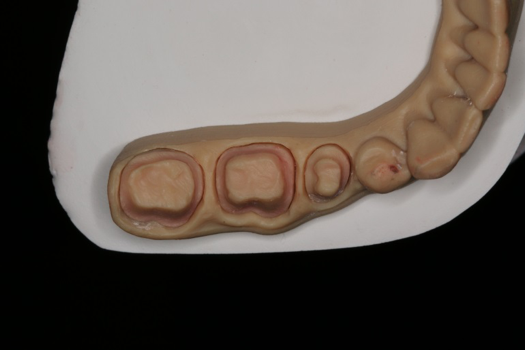

After completing an initial diagnostic appointment, a patient accepted three single-unit full-contour zirconia crowns that were milled from the digital impression and cut back for porcelain application. The application by a technician is analog dentistry. The ability of a dental laboratory to scan an analog crown-and-bridge impression is called converting an analog impression to a digital impression. The workflow after the conversion has become digitized. A dental model is virtually created with computer software, and a full crown proposal is fabricated for inspection virtually before the crown is milled (Figure 2). Due to the color of the digitized impression, the margins of the crown preparations are more easily and rapidly identified. The laboratory will also 3D print a working model, which will be used to develop the morphology of the final restoration by hand placement of porcelain (Figure 3). The decision to prescribe a full contour zirconia crown with cutback for porcelain application or complete full contour zirconia crowns lies solely on the attending dentist.9 A discussion with the patient before preparation of the teeth is imperative. After the discussion, the patient requested the zirconia copings with cutback and porcelain application for the posterior crowns (Figure 4 and Figure 5).

Fig 3. 3D-printed model.

Figure 3

Fig 4. Zirconia with cutback for porcelain application.

Figure 4

Fig 5. Occlusal view of completed zirconia with porcelain application on teeth Nos. 29, 30, and 31.

Figure 5